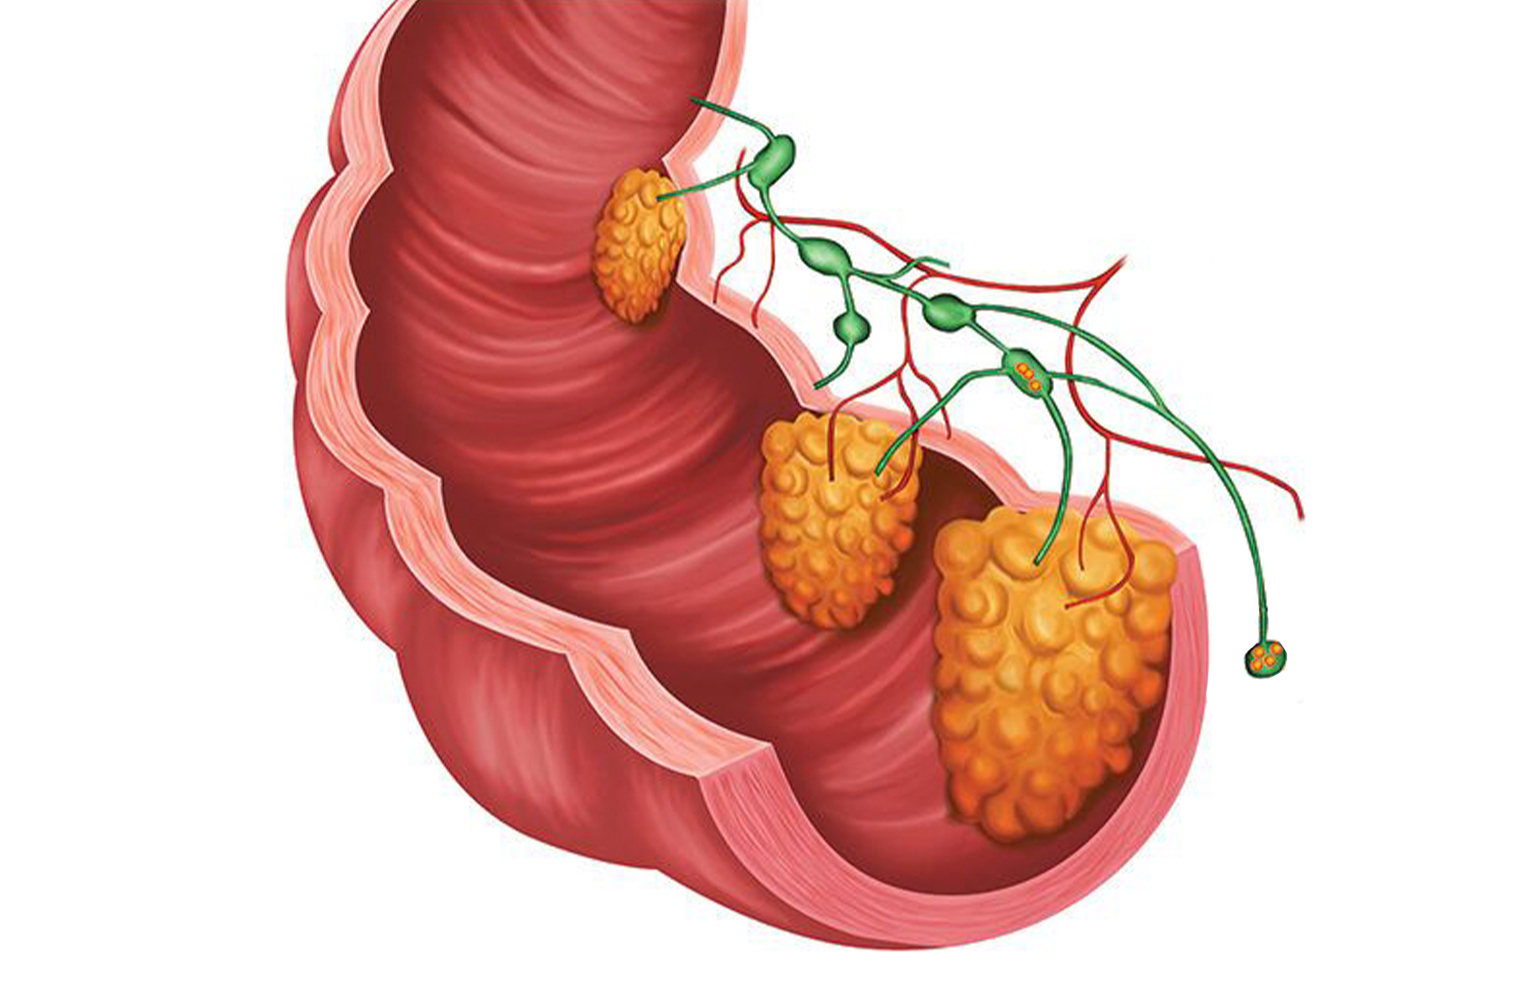

Detaylı BilgiKolon ve Rektum Kanseri

Kalın bağırsağın herhangi bir bölümünde ortaya çıkan kansere, kolon kanseri denmektedir. Eğer kanser rektumda lokalize ise rektum kanseri adını almaktadır.